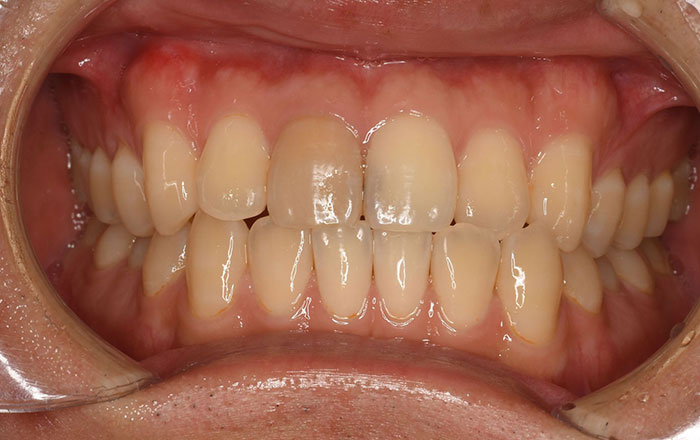

2.神経が死んでしまった歯・金属の詰め物による変色

2.金属の詰め物による変色

神経が死んでしまった歯は、栄養が行き届かなくなった歯は次第に黒く変色していきます。

また、銀歯の成分が溶け出すことにより、変色することがあります。

神経が死んでしまった歯は、ウォーキングブリーチという治療を行うことで白さを保つことができます。

銀歯の成分が溶け出してしまっている場合は、原因である銀歯を外し、セラミックなど、別の詰め物に変える必要があります。

また、歯茎が変色してしまった場合は、ガムピーリングで歯ぐきの着色が改善する可能性が高いです。